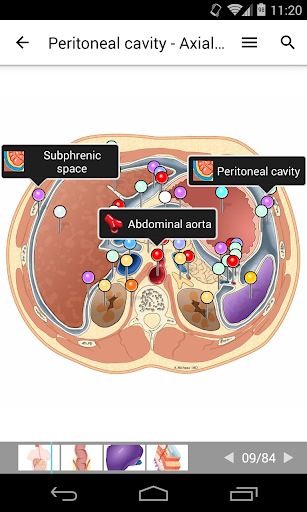

e-Anatomy memiliki lebih dari 26.000 gambar yang berisi serangkaian gambar dalam tampilan aksial, koronal, dan sagital serta radiografi, angiografi, gambar diseksi, bagan anatomi, dan ilustrasi. Semua gambar medis diberi label dengan cermat, lebih dari 967.000 label tersedia dalam 12 bahasa termasuk Terminologia Anatomica Latin.

- Gulir set gambar dengan menyeret jari Anda

- Perbesar dan perkecil

- Ketuk label untuk menampilkan struktur anatomi

- Pilih label anatomi berdasarkan kategori